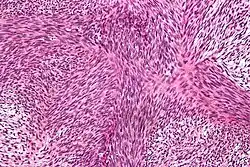

![]() | |

| Micrograph of malignant peripheral nerve sheath tumour with the typical herringbone pattern. H&E stain. | |